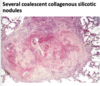

complicated CWP

simple CWP

silicosis